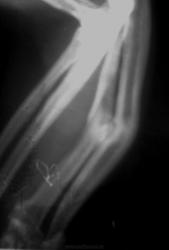

В возрасте одного года упал с высоты 8 этажа на газон, отделался оскольчатым переломом ср/3 диафизов лучевой и локтевой костей правой передней конености с угловым смещением.

Был интрамедуллярный остеосинтез. Через год извлечение стержня МОС. Снимков до и после операции к сожалению не сохранилось.

Данный снимок выполен через 8 лет, по другому поводу (рентген-неконтрастное инородное тело в гортани).

Выкладываю увеличенный фрагмент снимка и полный снимок.

Сейчас бодр и весел. Кончность с заметной угловой деформацией. Не болит, полностью функционирует.